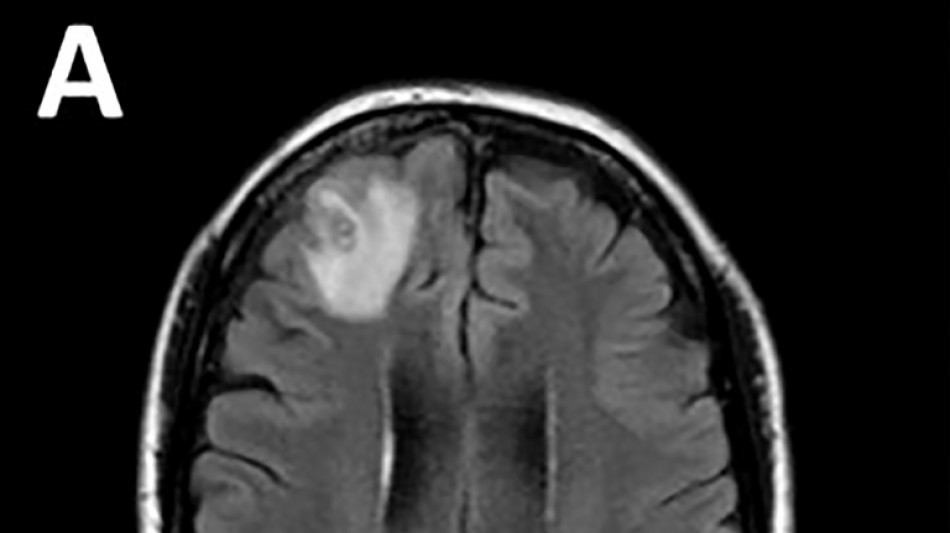

Médicos australianos hallan por primera vez una lombriz parásita en el cerebro de una mujer

Una lombriz parásita usualmente encontrada en serpientes fue retirada "viva y coleando" del cerebro de una mujer, algo que no se había visto en los registros médicos, informaron el martes médicos australianos.

Desconcertados, los médicos realizaron una resonancia magnética a una mujer australiana de 64 años después de que comenzara a sufrir lapsos de memoria y notaron una "lesión atípica" en el frente de su cerebro.

Era una lombriz de ocho centímetros llamada Ophidascaris robertsi, que según investigadores son parásitos comunes en canguros y pitones diamantina pero no en humanos.

"Este es el primer caso humano de una Ophidascaris en el mundo", afirmó el experto en enfermedades infecciosas Sanjaya Senanayake.

"Hasta donde sabemos, es también la primera vez que aparece en el cerebro de una especie de mamífero, humano o no", agregó.